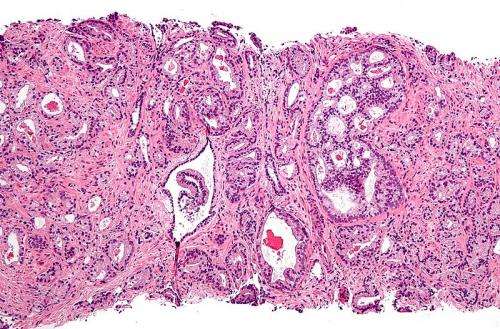

Micrograph showing prostatic acinar adenocarcinoma (the most common form of prostate cancer) Credit: Wikipedia